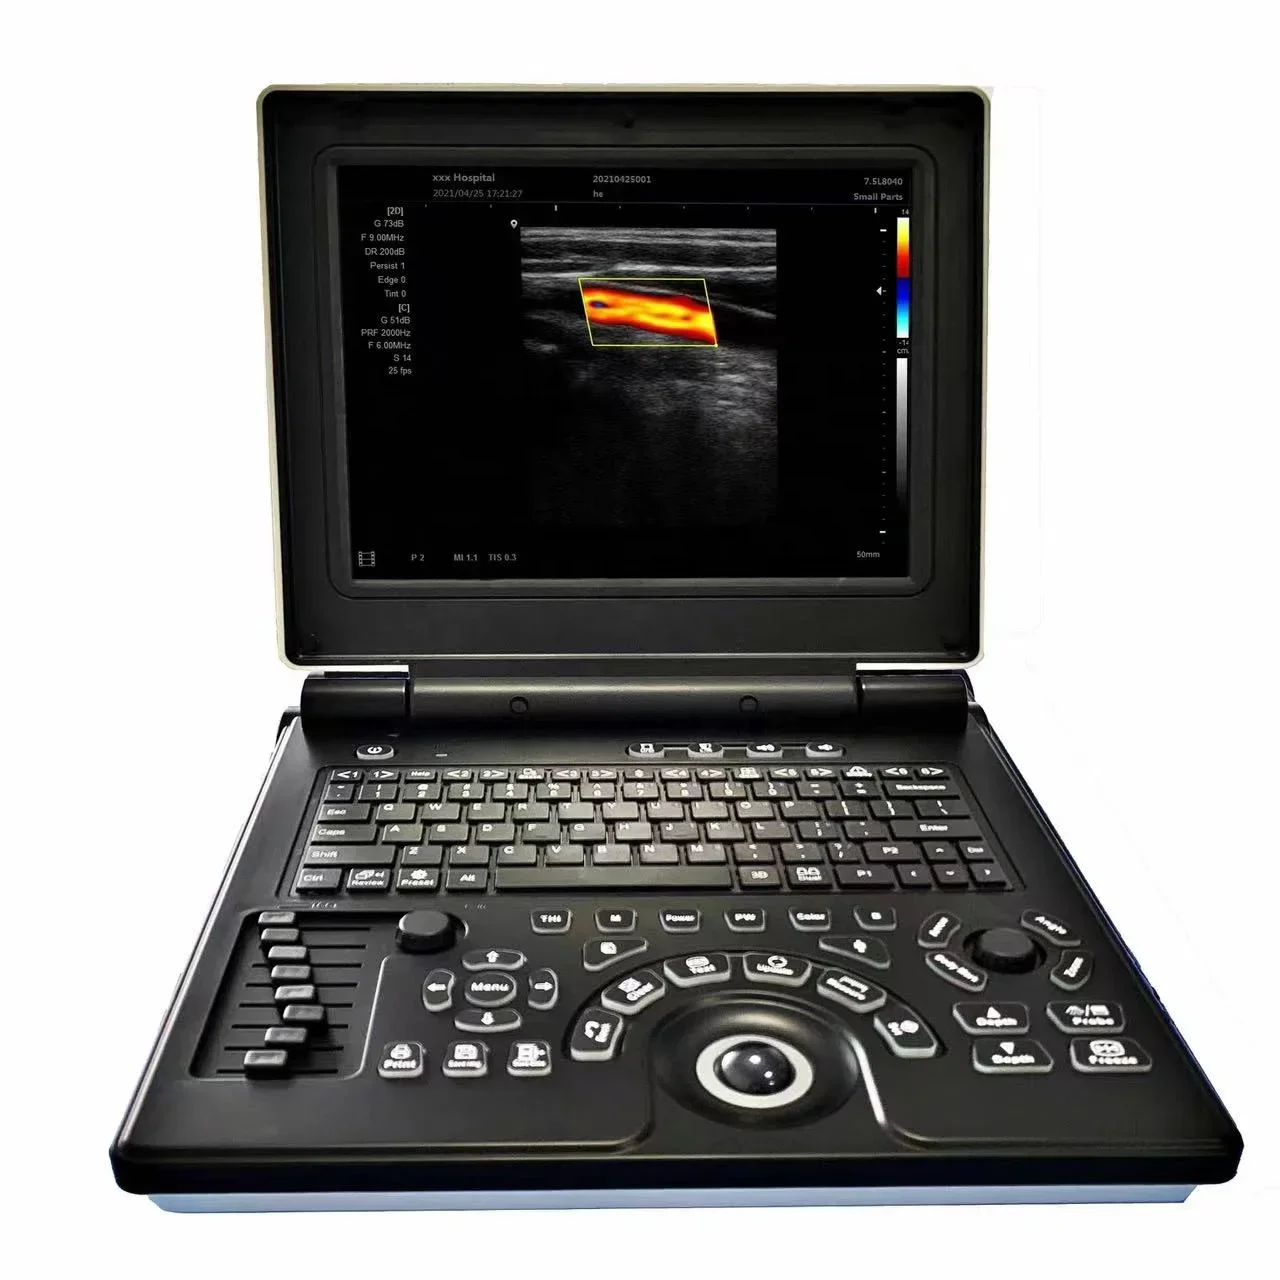

Small Full Digital Portable Ultrasound Equipment with Android/IOS Windows

Linear Probe Pictures: